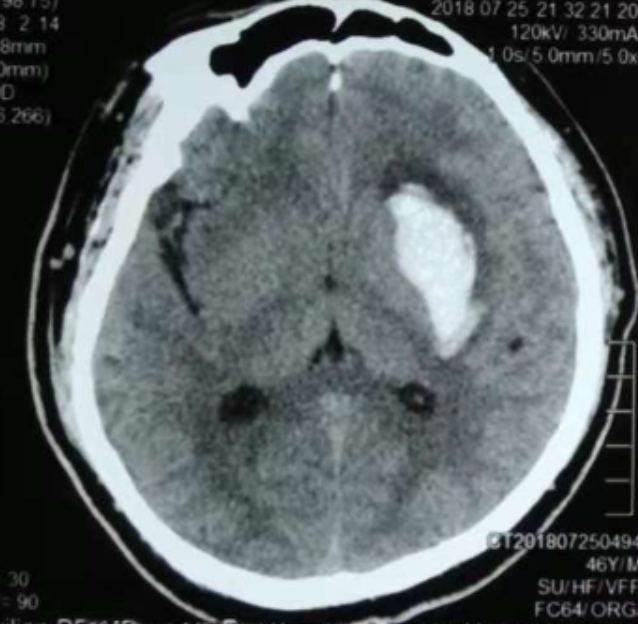

11月7日,中國(guó)醫(yī)科大學(xué)附屬第一醫(yī)院神經(jīng)外科順利開展首例國(guó)產(chǎn)神經(jīng)外科手術(shù)機(jī)器人輔助腦血腫抽吸手術(shù)。手術(shù)由該院神經(jīng)外科主任吳安華教授把關(guān),韓帥醫(yī)師主刀完成?;颊?個(gè)月前腦出血行保守治療,未手術(shù)。術(shù)前,患者言語(yǔ)障礙,只能說(shuō)只言片語(yǔ),語(yǔ)速緩慢;術(shù)后,患者語(yǔ)速增快,表達(dá)流暢。

3個(gè)月前CT:腦出血